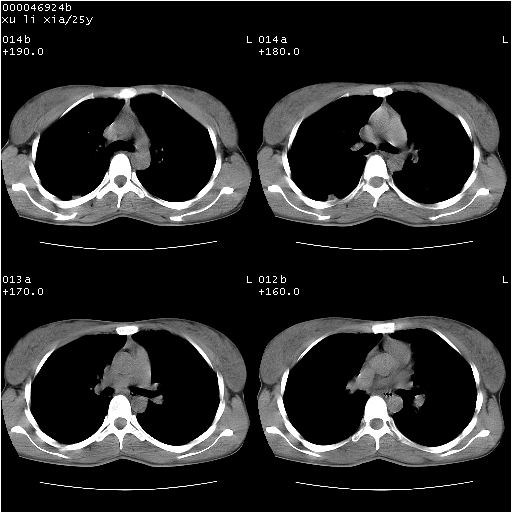

患者 女,25岁。因“左侧卵巢肿瘤”术前胸片偶然发现两肺病变。平素无明显不适,无呼吸系统症状及体征,无传染病史。

cr x线胸片提示:两肺感染性病变(结核可能性大)。

胸部ct轴位平扫(层厚10mm,螺距1.5,重建间隔10mm),图像如下:

(注:上级医院会诊胸部ct片——考虑为肺部真菌感染。)

病灶呈地图样分布于肺外围,与正常组织分界清晰+弥漫性磨玻璃影中见小叶间隔增厚呈碎石路样表现+年轻女性,无明显临床症状=肺泡蛋白沉积症?